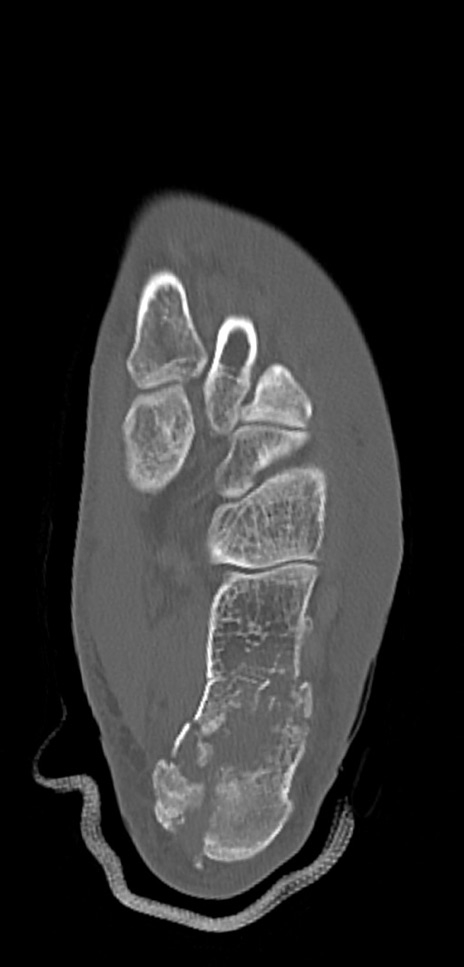

左足関節CT

矢状断像